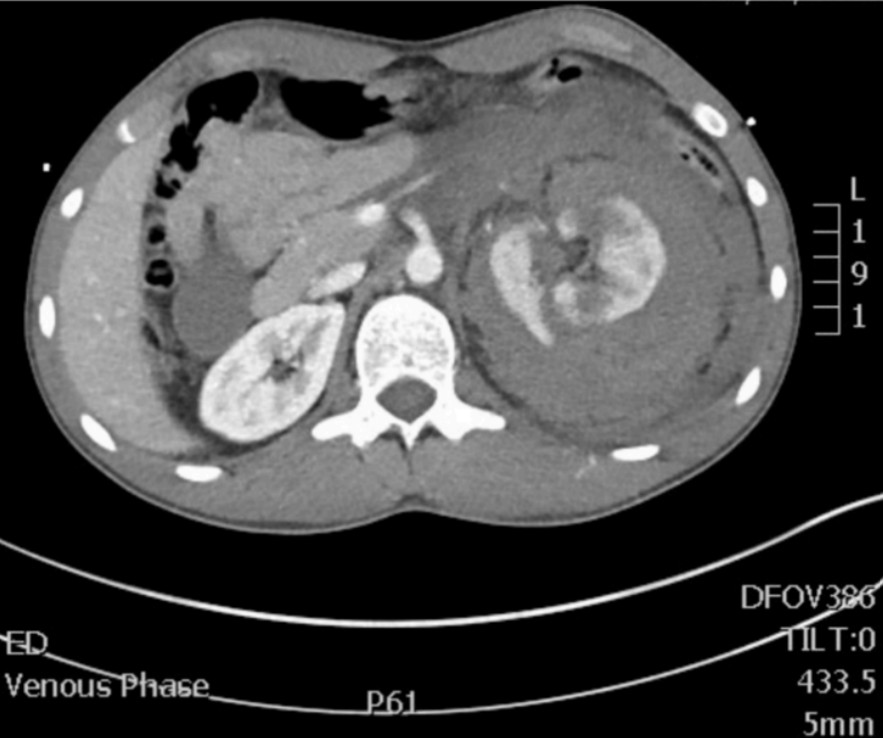

Renal trauma

A 26-year-old man has been brought to the ED after falling from a horse. A CT scan has been performed.